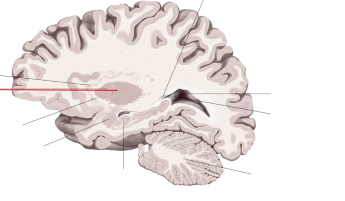

corpus callosum

lobus frontalis

lobus parietalis

lobus occipitalis

lobus temporalis

gyrus cinguli

sulcus centralis

sulcus cinguli

fornix